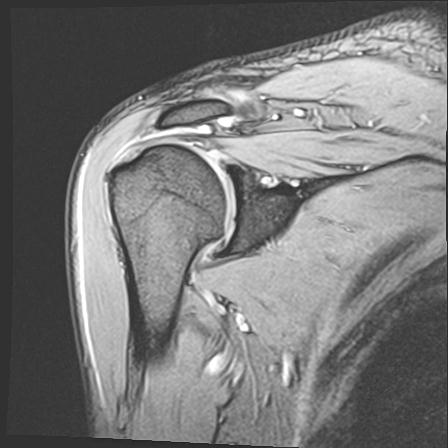

60058 3/9 11/4 右肩 2R+MRI 73歳男性 肩腱板損傷